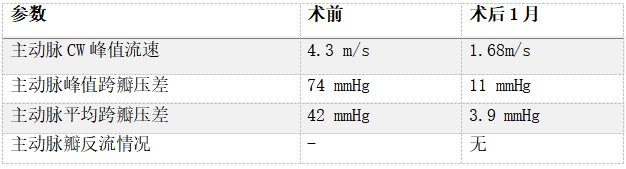

术后1月随访

1个月随访情况